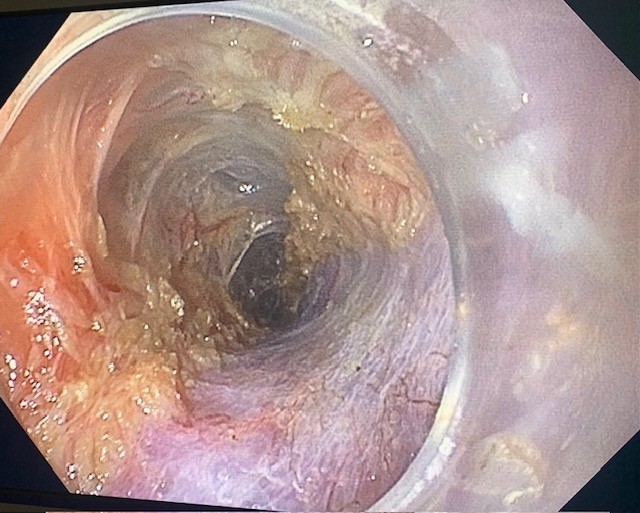

Zenker peroral endoscopic myotomy was performed under general anesthesia. EGD was performed and all the food contents from the pouch were removed (Fig. 2). A guidewire was passed through the esophageal lumen for identification during procedure. Saline with methylene blue was injected along the cricopharyngeal ridge and a mucosal incision was made along the ridge using a Triangular tip knife (TTJ Olympus, America) using ENDOCUTQ current (ERBE). Submucosal dissection was done to form a tunnel using spray coagulation and the esophageal mucosa and diverticular mucosa were separated from the cricopharyngeus muscle. Then a complete cricopharyngeal myotomy was performed using the same Triangular tip knife until the buccopharyngeal fascia was reached (Fig. 4 & 5). After complete hemostasis, the mucosal incision was closed using through-the-scope clips (Microtek). A total of five clips were used for the closure (Fig. 6).

Figure 5: Submucosal tunnel with complete myotomy of the cricopharyngeus.

Figure 5